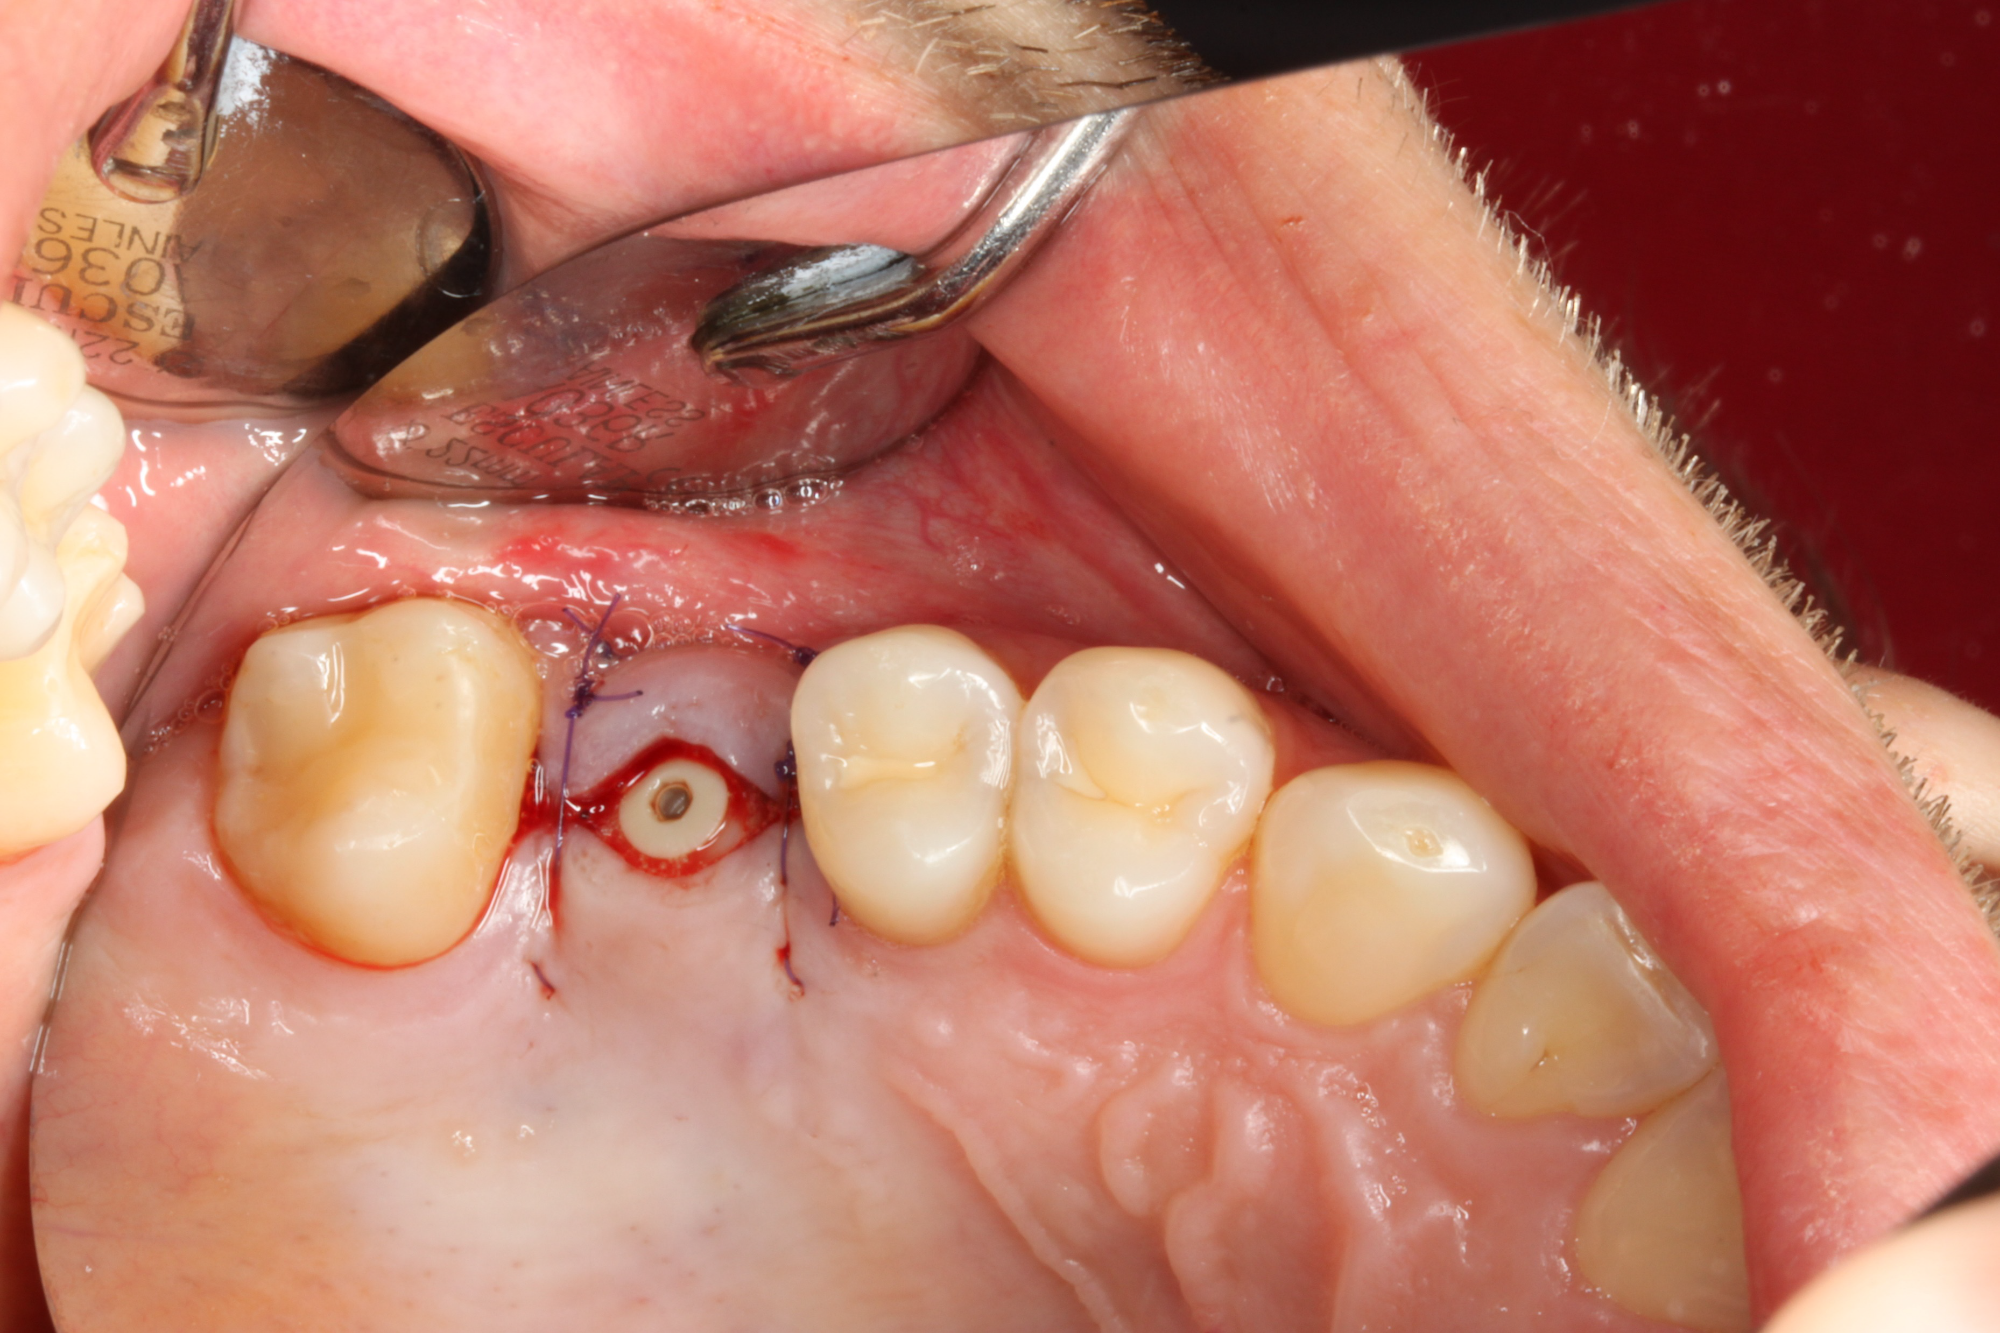

Die Implantat Entfernung in unserer Praxis

Bei der Implantat- Entfernung wird sehr genau gearbeitet, sodass keine Titanpartikel durch die Ausbohrung im Knochen zurückbleiben. Die Entfernung von Titanimplantaten erfordert nicht nur eine fachmännische chirurgische Technik, sondern auch eine umfassende Nachsorge (z.B. Schwermetallausleitung), um eine schnelle Genesung zu gewährleisten.

Unsere Praxis ist mit neuen Technologien und Materialien ausgestattet, um diesen Prozess so schonend wie möglich zu gestalten. In der Regel ist es möglich, die Titanimplantate aus dem Knochen herauszudrehen, ohne einen Knochendefekt zu hinterlassen.

Nach der Entfernung der Titanimplantate können bei gesundem Knochen Keramikimplantate sofort gesetzt werden. Mit dem unmittelbaren Austausch von Titan zu Keramik wird Zeit gewonnen, so kann das neue Implantat in dieselbe Stelle eingearbeitet und Knochenverlust vermieden werden.